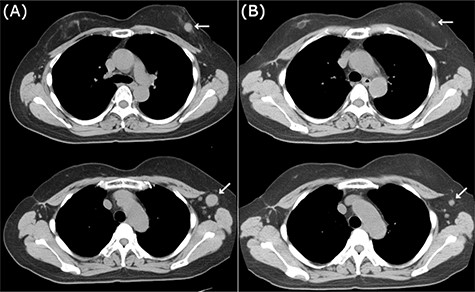

CT images of right breast tumor before and after treatment. (A) Chest CT displaying nodules in the right breast (top, arrowhead) and lymph node swelling in the right axilla (bottom, arrowhead); (B) after administration of NAC, the primary tumor (top, arrowhead) and axillary lymph nodes (bottom, arrowhead) displayed a clear reduction in size.

Neoadjuvant chemotherapy (NAC) was performed with four cycles of 5-fluorouracil (500 mg/m2), epirubicin (100 mg/m2) and cyclophosphamide (500 mg/m2) (FEC100 regimen), which showed a favorable response on imaging (Fig. 2B). She underwent surgery without taxane because she enrolled in a clinical trial (University Hospital Medical Information Network (UMIN) Clinical Trials Registry No.: R000029940) [4]. Postoperative treatment depends on the histopathological results. Based on the patient’s BRCAness score (0.6), she underwent breast-conserving surgery, and axillary lymph node (LN) dissection owing to a positive sentinel node biopsy. Pathological analysis demonstrated almost pCR in the breast and only a few degenerated carcinoma cells remaining in the stroma, with no metastatic carcinoma cells in the dissected LNs. Thus, she was sequentially administered 12 cycles of weekly paclitaxel and 50 Gy of radiotherapy.